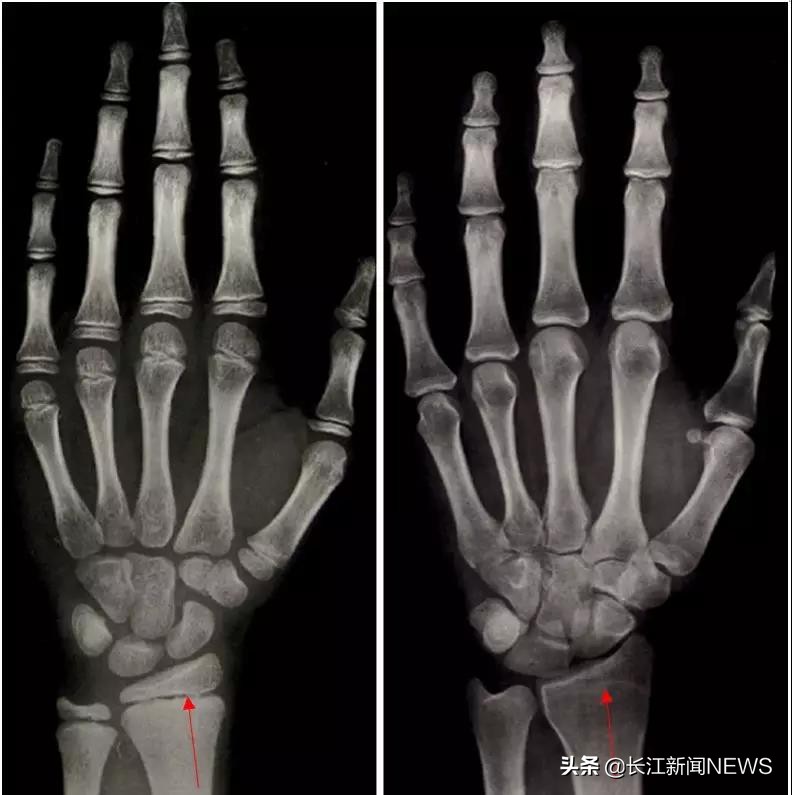

这里给大家介绍儿童内分泌医生最经常做的检查:左手骨龄片。

左图是男性8岁7个月的骨龄片,右图是17岁的骨龄片,从8岁7个月的骨龄片上可以看到,红箭头所指的这个缝隙我们叫做骨骺,理论上说只要骨骺没有闭合,就说明还有生长空间;而右边17岁骨龄片中的红箭头所指的地方骨骺已经闭合,就可以判断基本不会再长高了。

(中国人手腕部骨龄标准—中华05及其应用)